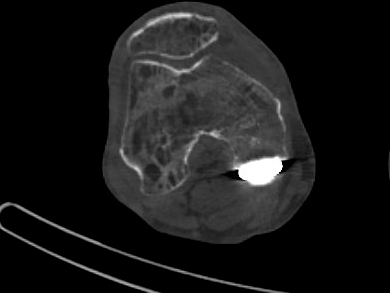

L’imagerie vient renforcer le diagnostic : la scintigraphie osseuse montre classiquement une hyperfixation dans la phase osseuse, tandis que l’IRM peut révéler un œdème médullaire, une déminéralisation mouchetée et des signes inflammatoires périarticulaires. Ces examens permettent de confirmer le diagnostic en cas de doute clinique ou d’évolution atypique.